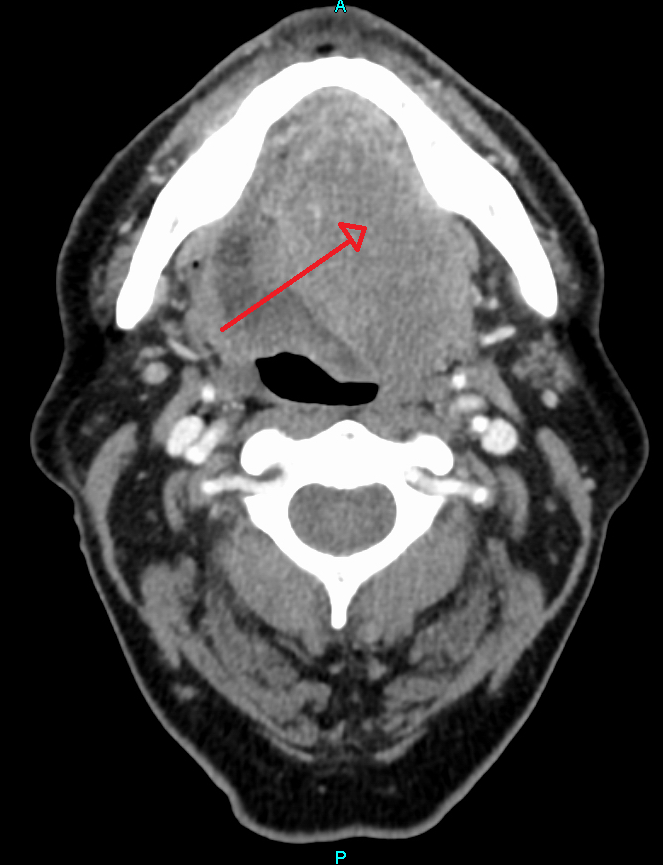

Squamous Cell Carcinoma

Squamous cell carcinoma (SCC) is the second most frequently diagnosed cancer worldwide.

Squamous cell carcinoma (SCC) accounts for about 30% of cancer cases in men and 20% of cases in women.

Two important risk factors for squamous cell carcinoma (SCC) are alcohol and tobacco use.

Invasive squamous cell carcinoma (SCC) may develop from oral leukoplakias and erythroplakias, which are precancerous diseases.

Although they can appear anywhere in the oral cavity epithelium, these lesions typically grow at the mouth’s floor.

Histologically, squamous cell carcinoma (SCC) is identified by alterations in the stratified squamous epithelial layers, such as invasion into the underlying connective tissue and hyperkeratosis, parakeratosis, acanthosis, keratin pearls, and dysplasia.